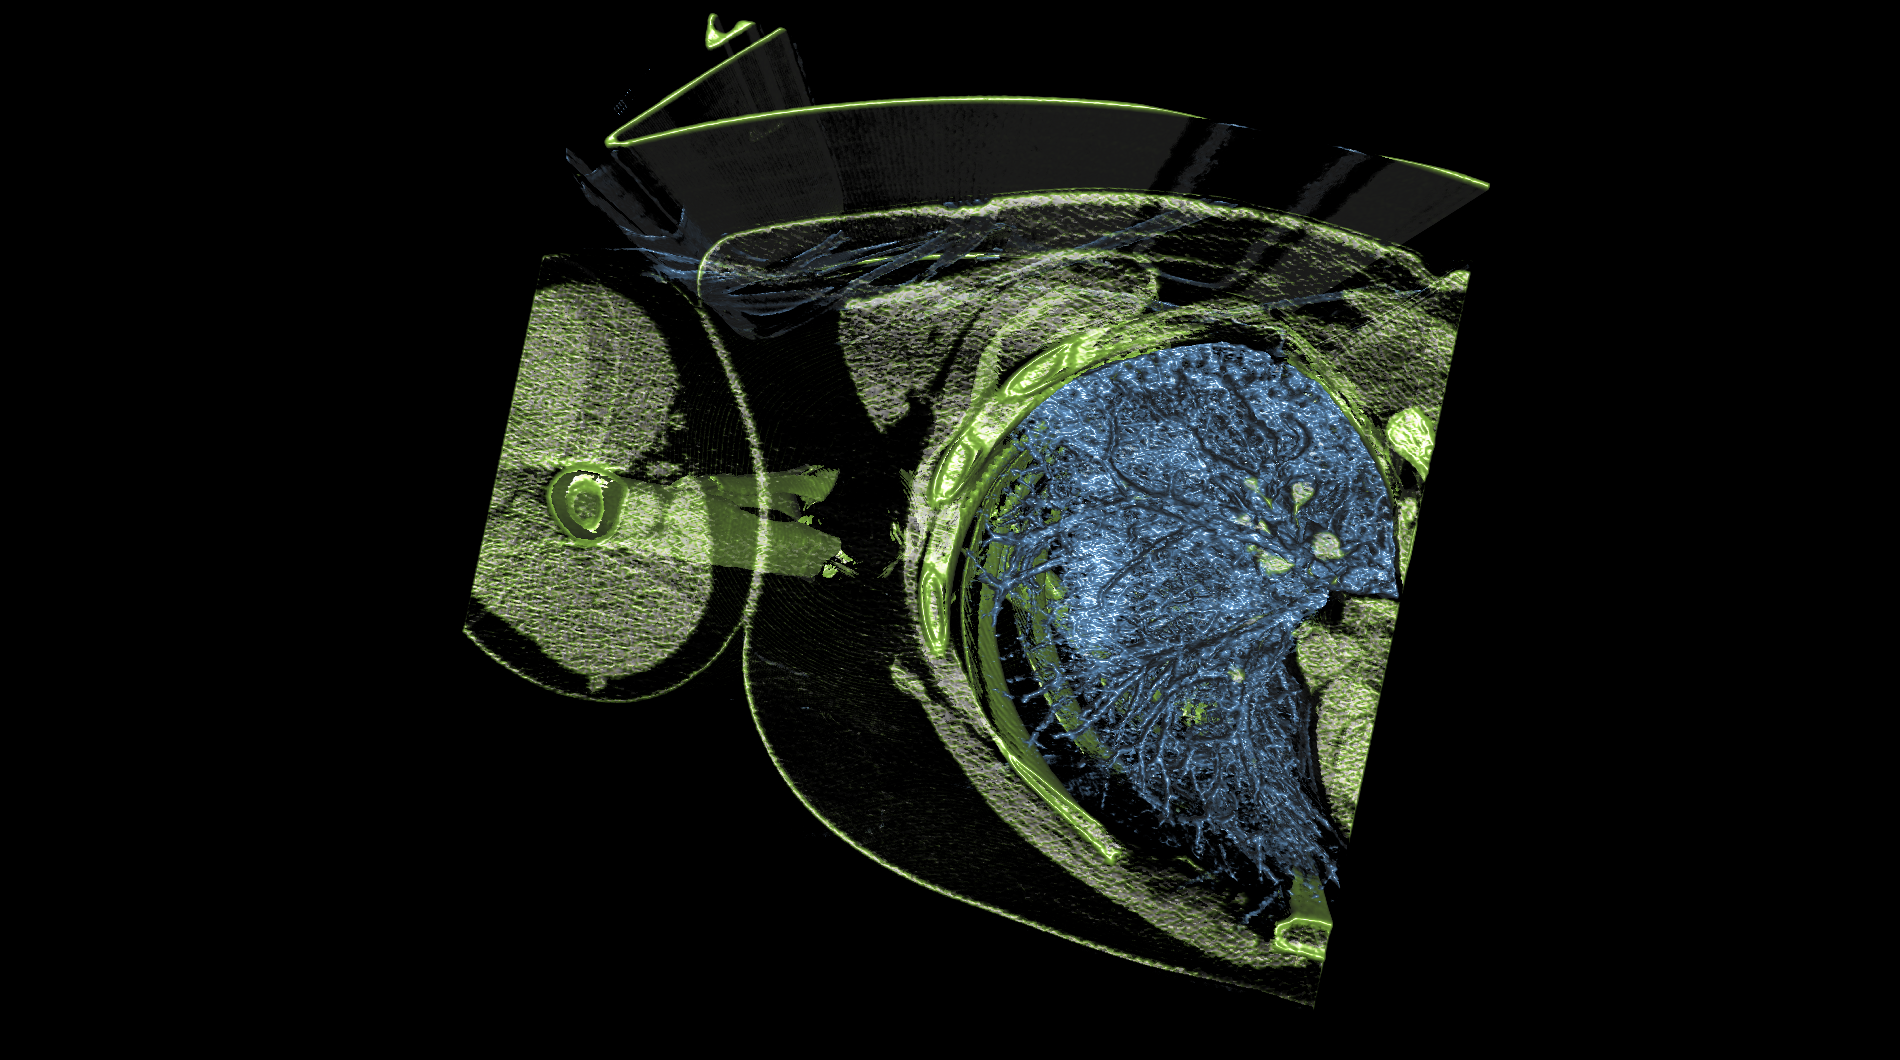

| The medical-04 workload evaluates medical visualization techniques using the Tuvok library and OpenGL API. It features slice rendering and raycasting with 1D and 2D transfer functions, exploring datasets from a beating heart, brain, and alligator. Clipping planes and varying voxel densities test performance in medical imaging workflows, simulating scenarios like MRI and CT analysis. | |||

| Composite Score: | 271.71 | ||

| Graphics Renderer: | RTX 6000 Ada Generation | ||

| Index | Description | Weight | Result (FPS) |

Raycasting of a broken arm with 2D transfer

Raycasting of a broken arm with 2D transfer

|

10.00 |

321.68

|

| 8 |

Raycasting of a broken arm with 2D transfer and clipping plane

Raycasting of a broken arm with 2D transfer and clipping plane

|

10.00 |

499.83